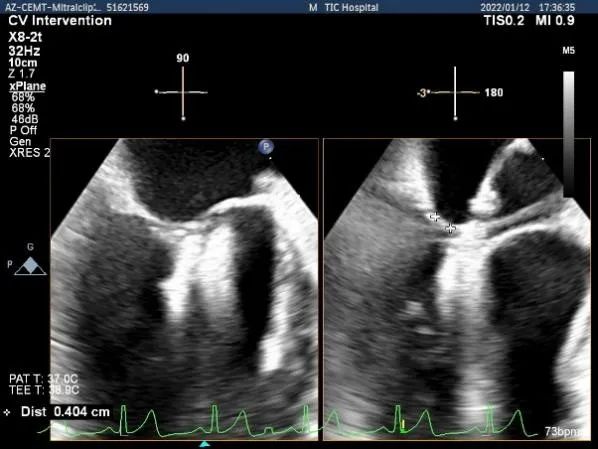

TEE Bicom view:二尖瓣AC区为主(累及部分1区)脱垂并腱索断裂。

确定房间隔穿刺点:中部靠后

穿刺点高度测量:4.09cm,由于病变部位靠前交界,穿刺高度尚可